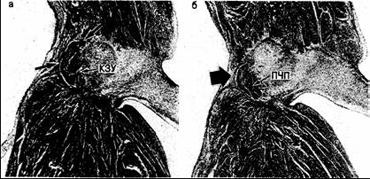

Рис. 11. Микрофотографии срезов из серии,представленной на рис.10 (продолжение). а - соединение компактной зоны узла (КЗУ) и проникающей части пучка; ось проходит между фиброзным трикуспидальным кольцом и центральным фиброзным телом,являясь здесь АВ -узлом, ибо она осуществляет контакт с переходной клеточной зоной предсердия как на поверхности (светлая стрелка),так и в глубине перегородки (черная стрелка); б - тело узла,расположенного полуовалом напротив фиброзного кольца (очерчен точками), причем вокруг компактной зоны узла находится переходная клеточная зона (в пределах пунктирных линий).Обратите внимание на сухожилие Тодаро (СТ) у верхнего края среза

Рис. 12. Микрофотографии, показывающие различие между компактной зоной узла (КЗУ) и проникающей частью пучка (ПЧП) в области атриовентрикулярного соединения, представленного на рис. 10 и 11. а - ось осуществляет контакт с тканями предсердия (между стрелками) и, следовательно, является компактной зоной узла; б - гистологически идентичная ось входит в центральное фиброзное тело, где фиброзная ткань (стрелка) препятствует ее контакту с межпредсердной перегородкой. Следовательно, это проникающая часть АВ-пучка